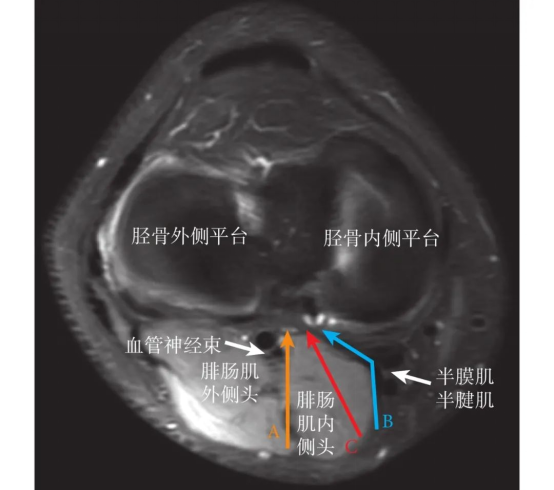

▲手术示意图(C为微创安全手术入路)

改良膝关节微创安全入路,在膝关节后内方劈开腓肠肌内侧头,利用腓肠肌内侧头的外半部对腘窝处神经血管加以遮挡,起到保护作用,且通过拉开腓肠肌内侧头的外半部,距离骨折处更近,暴露更清晰,可以达到更好的复位内固定效果。总体来说,改良膝关节微创安全入路治疗后交叉韧带胫骨止点撕脱骨折操作简单,临床疗效确切。